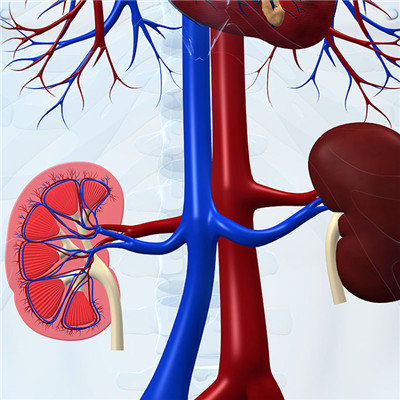

Got nephritis serious? This is what many patients are thinking. Some patients don't even know that they will get this disease. In fact, different patients with nephritis have different manifestations. Some patients will have edema, low back pain and weakness. Some patients have nephritis without any obvious reaction. It's not easy to find it. No matter what symptoms, if they get nephritis and don't treat it for a long time, It may eventually lead to uremia. So for patients with nephritis, if found their own condition, must be treated as soon as possible.

In addition, patients with chronic nephritis often appear edema, which can be used as a standard for the diagnosis of this disease. When you get up in the morning, you will see swelling around your eyes and face, and serious edema will appear all over the body. So found that he appeared edema, must go to the hospital for examination, just in case

Medical experts have reminded that we must attach great importance to nephritis. Once diagnosed with nephritis, early treatment is the most critical. Patients with nephritis often have hypertension. For patients with chronic nephritis, hypertension will occur sooner or later, which may be persistent or intermittent.

For many patients with nephritis, if you can early detection, and take the correct treatment measures, it can avoid the occurrence of uremia, at the same time for patients with nephritis, a good living habits is very important, and find yourself sick after not nervous, as soon as possible to take the right treatment is the first priority.